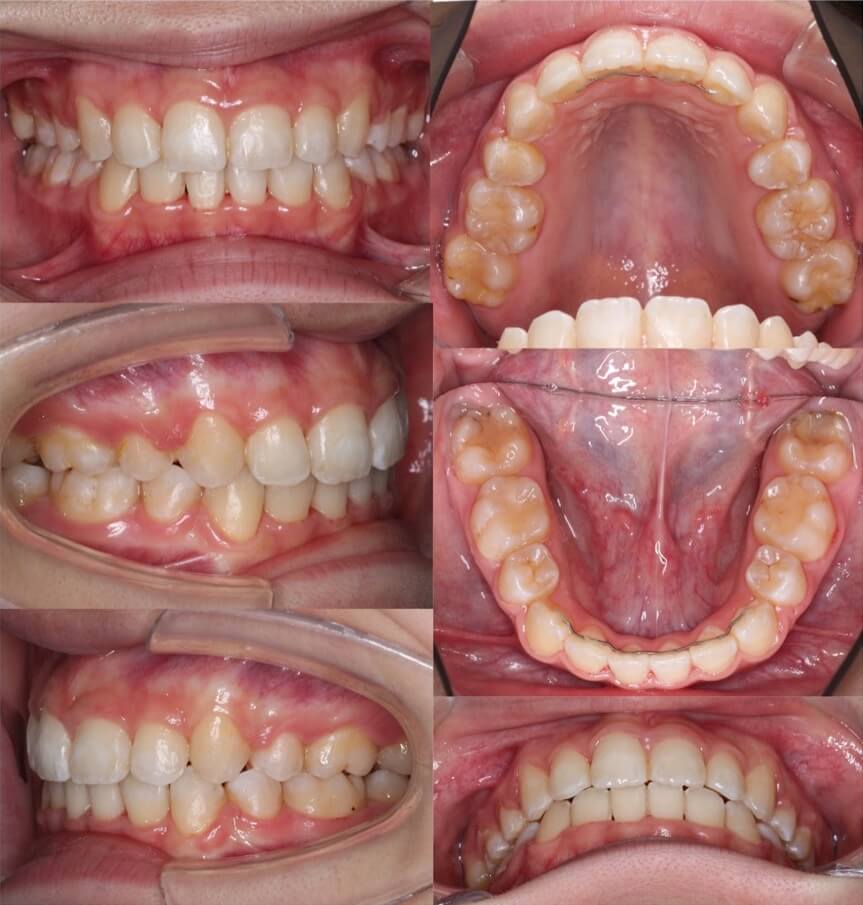

「あご先ができた」

大学生女性・唇側矯正・下あご後退型

<症例概要> 難易度:★★★☆☆

主訴:口元の突出

年齢・性別:大学生女性

住まい:千葉県八千代市

症状:下顎後退・上下顎前歯唇側傾斜

治療方針:抜歯空隙の閉鎖(最大固定)

治療装置:唇側矯正装置

固定:歯科矯正用アンカースクリュー(上顎頬側x2)

抜歯:上下第一小臼歯(計4本)

治療期間:2年2か月

リテーナー:上下プレートタイプ+フィックスタイプ

治療費用:968,000(税込)

代表的副作用:痛み・治療後の後戻り・歯根吸収・歯髄壊死・歯肉退縮

▶︎その他の副作用

アンカースクリューを使用して、最大限に上下の前歯を後ろに引っ張りました。前歯を後ろに引く量は事前にレントゲン分析による横顔のシミュレーションを行って決定します。このように最大限後方移動させる場合は、アンカースクリューなどの固定源の追加が必要になります。治療後は、あごのしわがなくなり、口元がかなり引き締まりました。